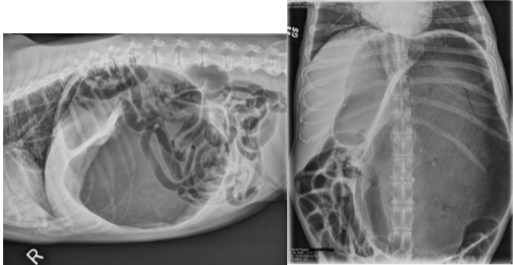

- Radiograph/X-rays (once patient is stabilized)-right lateral abdominal-> reveals pathognomonic compartmentalization of stomach (presence of dilation and/or volvulus).

- Dorsal ventral view- may help confirm the disease